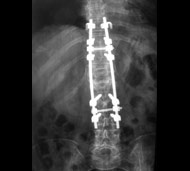

Мета операції - стабілізація хребта металевими конструкціями (імплантантами). Наша клініка була першою в СНД, яка застосувала сучасні конструкції при переломах хребта. Нині ми використовуємо імпортні конструкції типу CD Horison Legacy (США), Atlantis (США), Sextant (США), Socore (Франція). Операції вимагають складної рентгенівської техніки та спеціального інструментарію. При неускладнених переломах хребта хворі можуть ходити після таких операцій уже на другий - третій день. Також в Міжнародному центрі нейрохіургіі вперше в Україні впроваджено метод мініінвазивних операцій при переломах хребта.